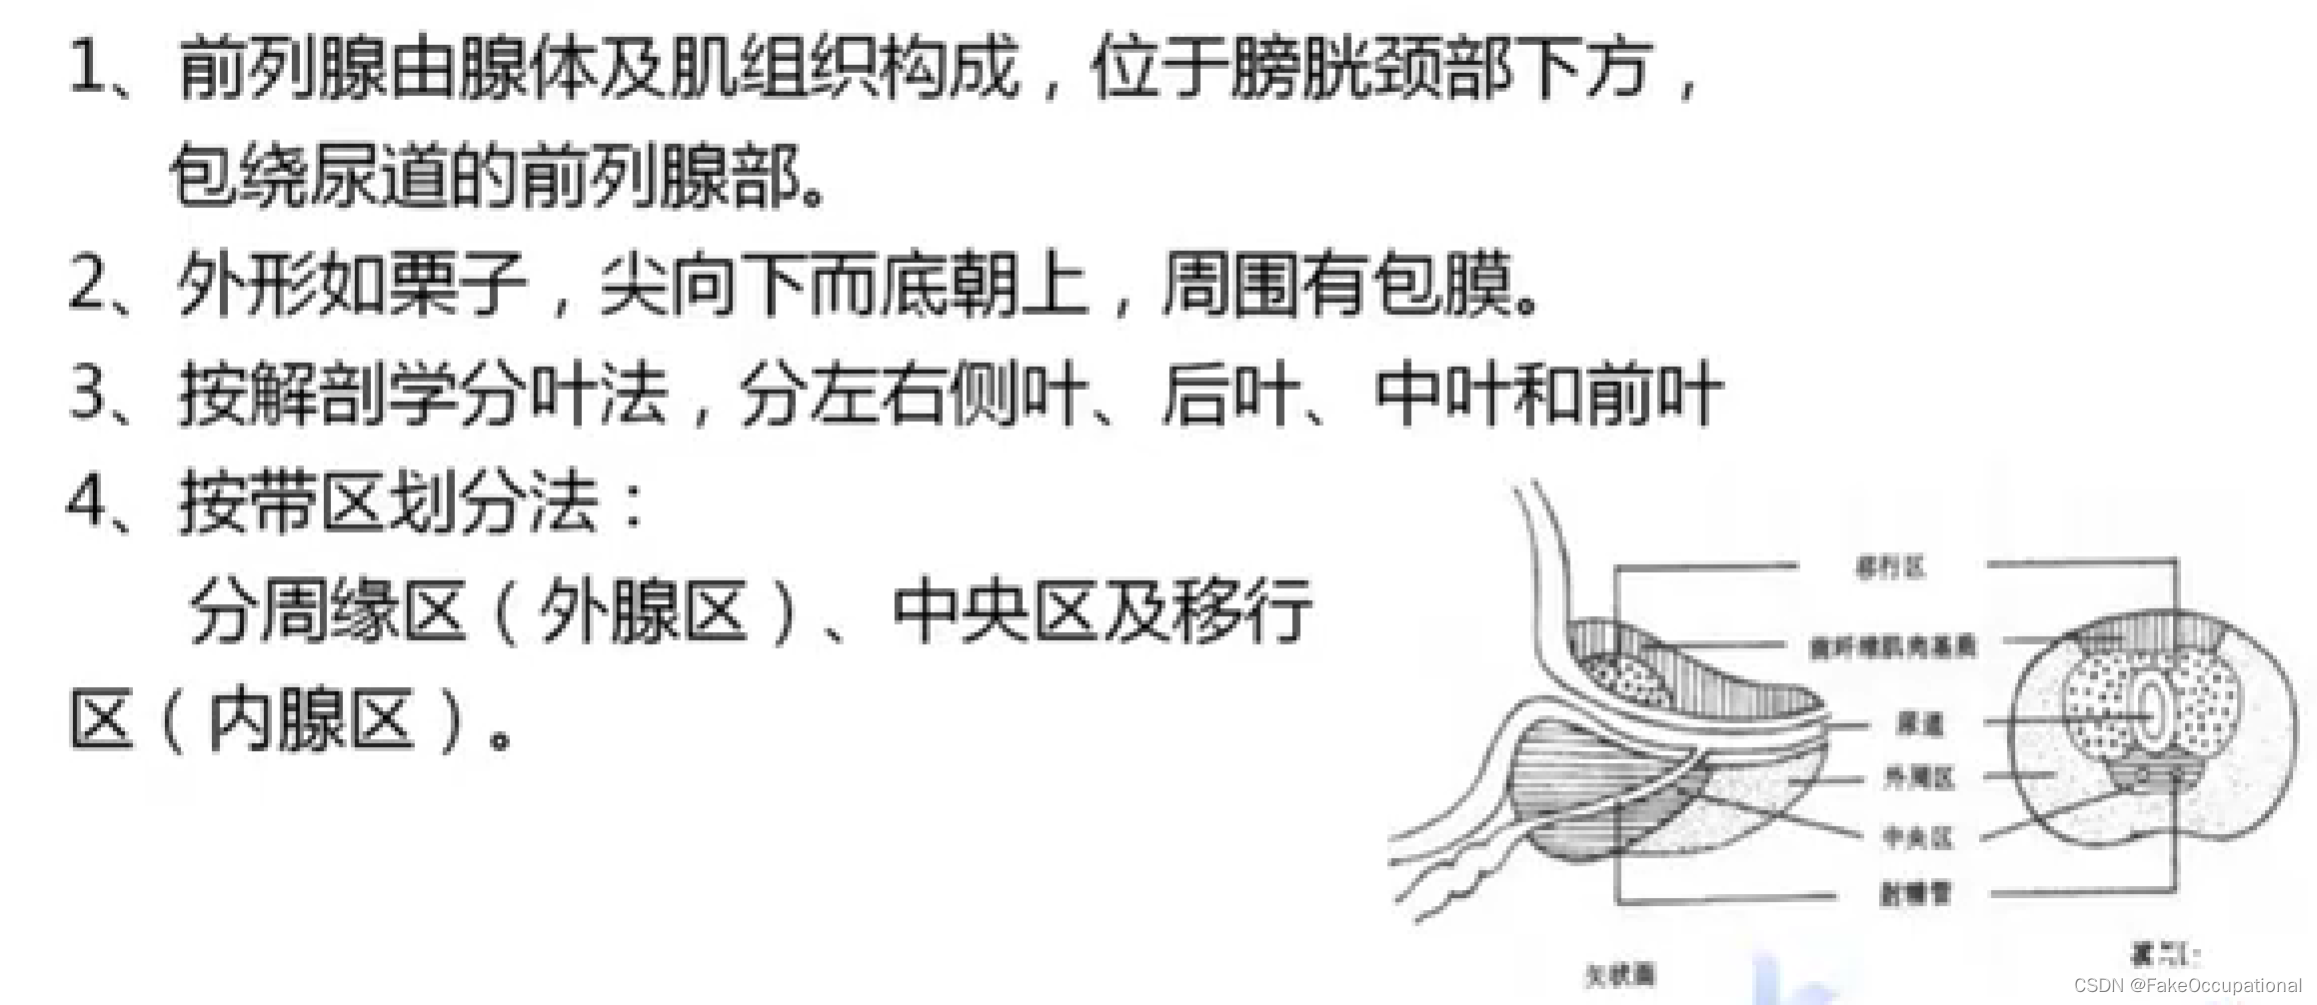

前列腺超声

检查方法

1、经腹部检查

仰卧位,也可采用侧卧位或截石位。探头放置于耻骨上,利用充盈膀胱作为透声窗

2、经直肠检查

方法同经直肠探测膀胱,是前列腺探测的最佳方法

3、经会阴部检查

取左侧卧位或膝胸位探头在会阴部或肛门前缘加压扫查

探头使用

1、经腹壁探测

凸阵或扇形超声探头,成人选用频率3.5MHZ儿童选用频率5.0MHz

2、经会阴探测

小凸阵或扇形超声探头,成人选用频率3.5MHz儿童选用频率5.0MHz。

3、经直肠探测

选用双平面直肠探头或端射式直肠探头探头频率50MHz~10.0MHZ。